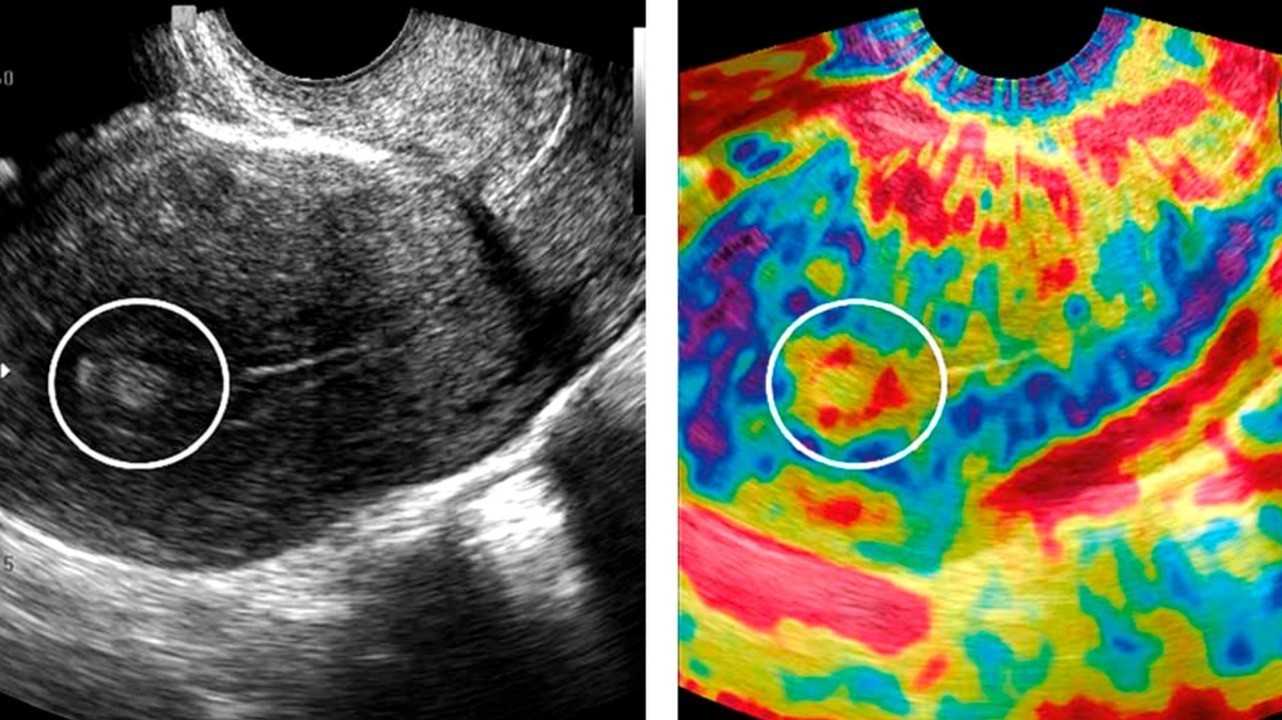

УЗИ (ультразвуковое исследование)

Это наиболее доступный диагностический метод, который используется и для скрининговых исследований. Трансвагинальное УЗИ позволяет выявить новообразование не только в теле, но и в шейке матки.

Полипы на снимке УЗИ. Фото: Prz Menopauzalny / Open-i (CC BY-NC-ND 3.0)